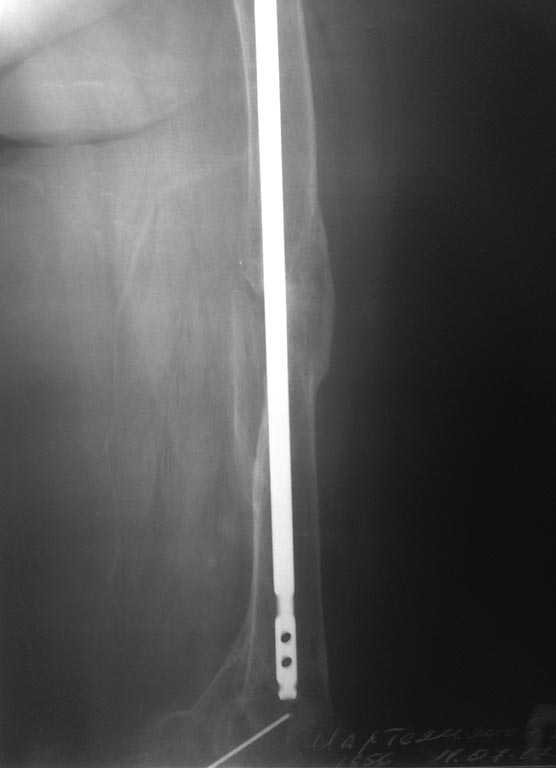

[Ortho] Удаление стержня из бедра перед эндопротезированием?

Вложение не в текстовом формате было извлечено…

Имя     : IMG_6570.JPG

Тип     : image/jpeg

Размер  : 31163 байтов

Url     : http://weborto.net:8080/pipermail/ortho/attachments/20170725/b3d50562/attachment-0004.jpeg